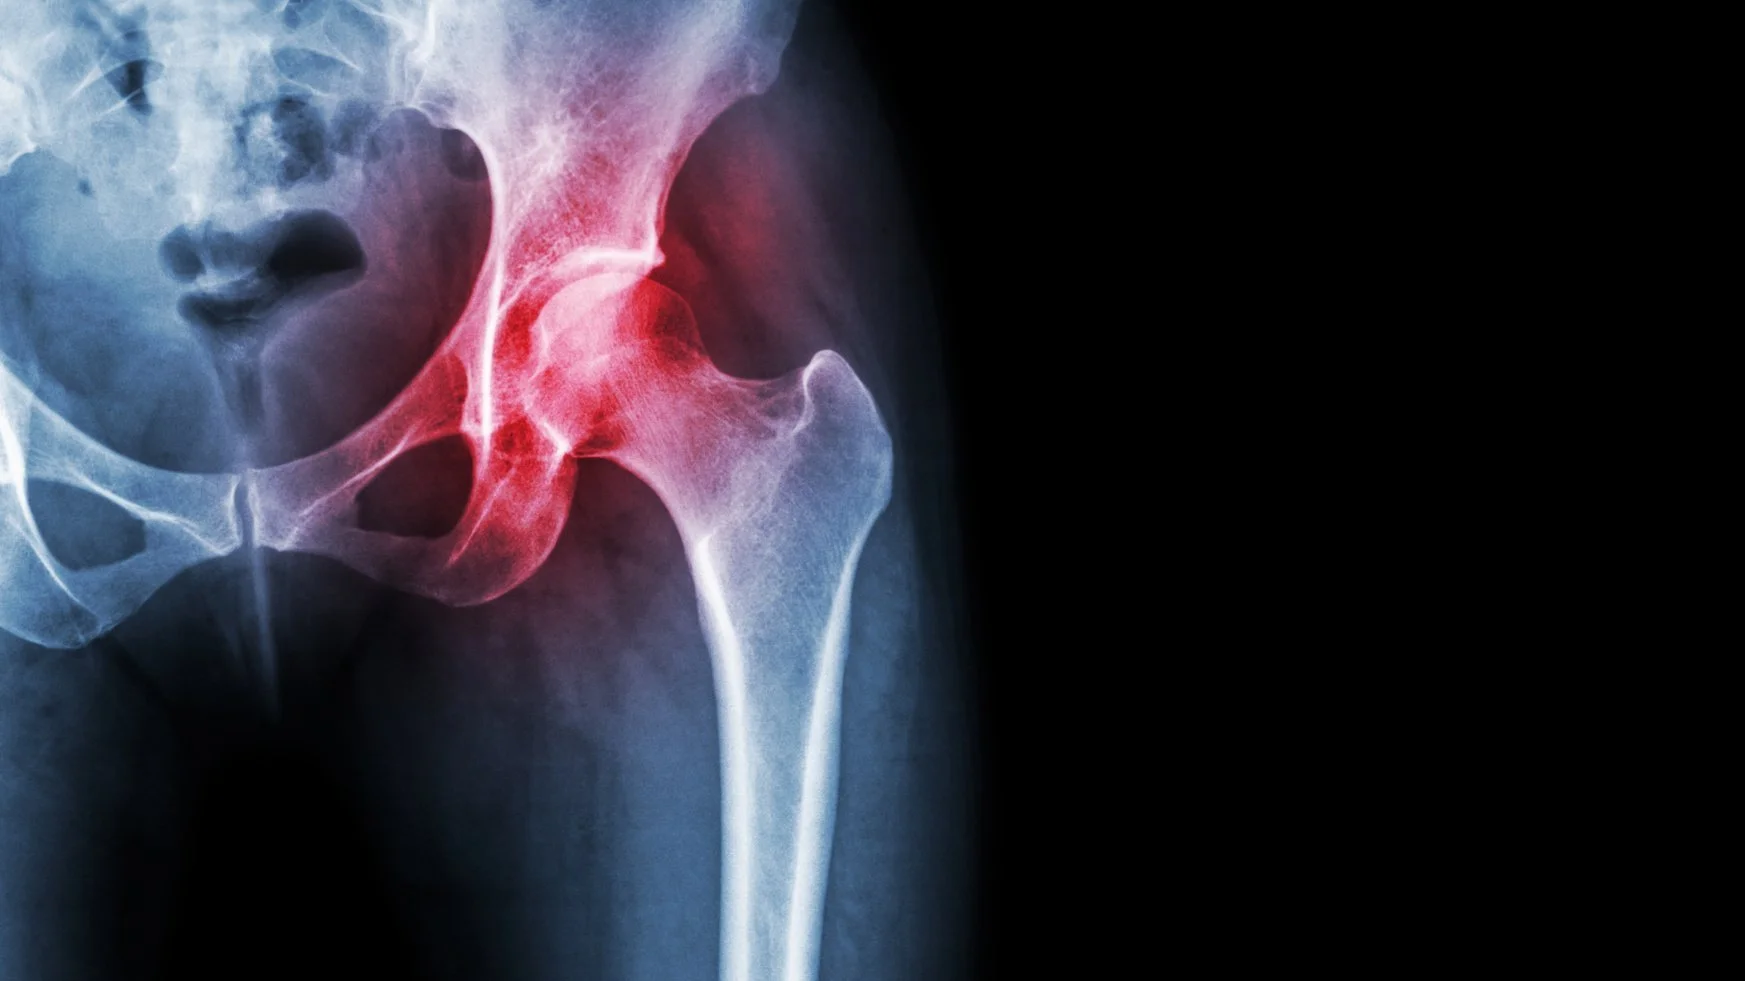

Artrose wijst op slijtage van het gewrichtskraakbeen dat het bot bedekt, artritis is een ontsteking van het gewricht of het gewrichtskapsel. Artritis kan tot artrose lijden. Artrose wijst op de slijtage van het gewricht waarbij het kraakbeen dat de botten over mekaar doet glijden progressief verdwijnt. Het heupgewricht wordt frequent aangetast.

Artrose (slijtage) van de heup. Artrose is een aandoening van de gewrichten. Het komt vaak voor in het heup- en kniegewricht. Het bot in een gewricht is bekleed met een laagje kraakbeen. Dat zorgt ervoor dat de gewrichtsvlakken soepel ten opzichte van elkaar kunnen bewegen. In het geval van de heup: dat de kop soepel kan draaien in de kom.